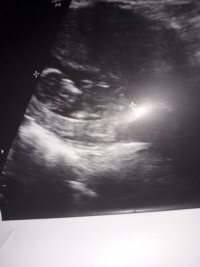

nub çıkıntısının üzerinde imleç var cinsiyet anlaşılmıyor ilk sayfayı incelemenizi öneriyorum görselin kalitesi konu içinde yer alan görselle aynı olmalıdır.

Dun malatyada verildi 12 +4 gunluk lutfen yorumlayin

Görsellerde nub çıkıntısı belli değil . Ultrasonu yapan doktor cinsiyeti hakkında bilgi vermiştir mutlaka ama şunu belirtmeden geçmeyeyim. Bu haftalarda cinsiyet tahmininde yanılma payı çok yüksek 17-19 ve 20 ci haftalarda bebeğin cinsiyetini net olarak öğrenebilirsiniz.